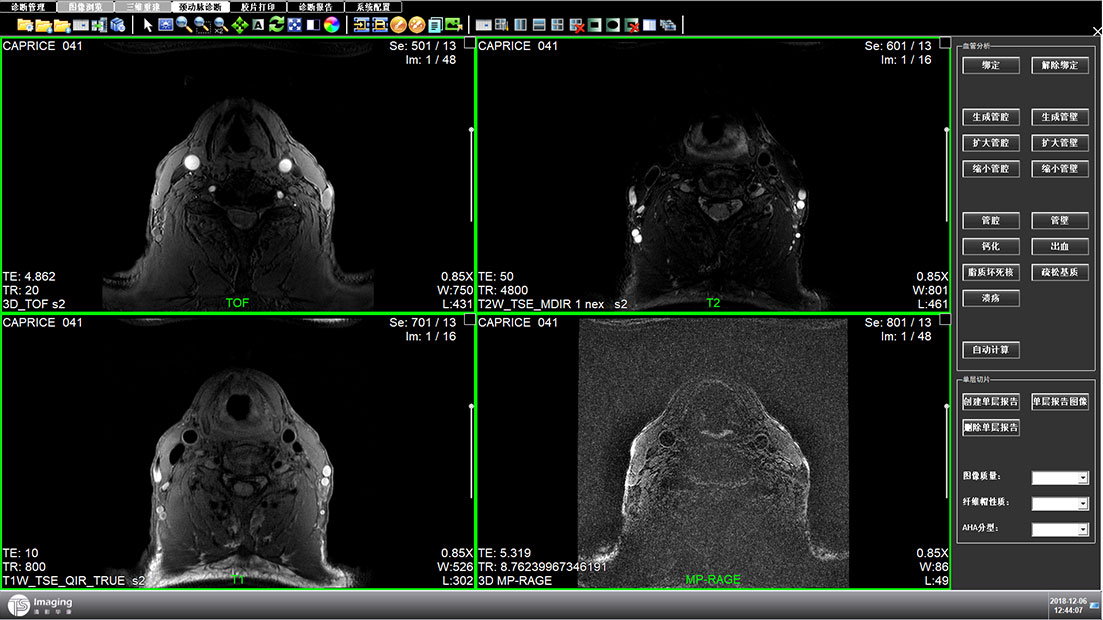

頸動脈診斷頁面

頸動脈診斷頁面整體布局和三維重建比較相似,最大的區別是右側的操作區域,血管分析都為按鍵操作,通過間隔的大小分成三部分。單層切片除了按鍵還有下拉菜單的操作。